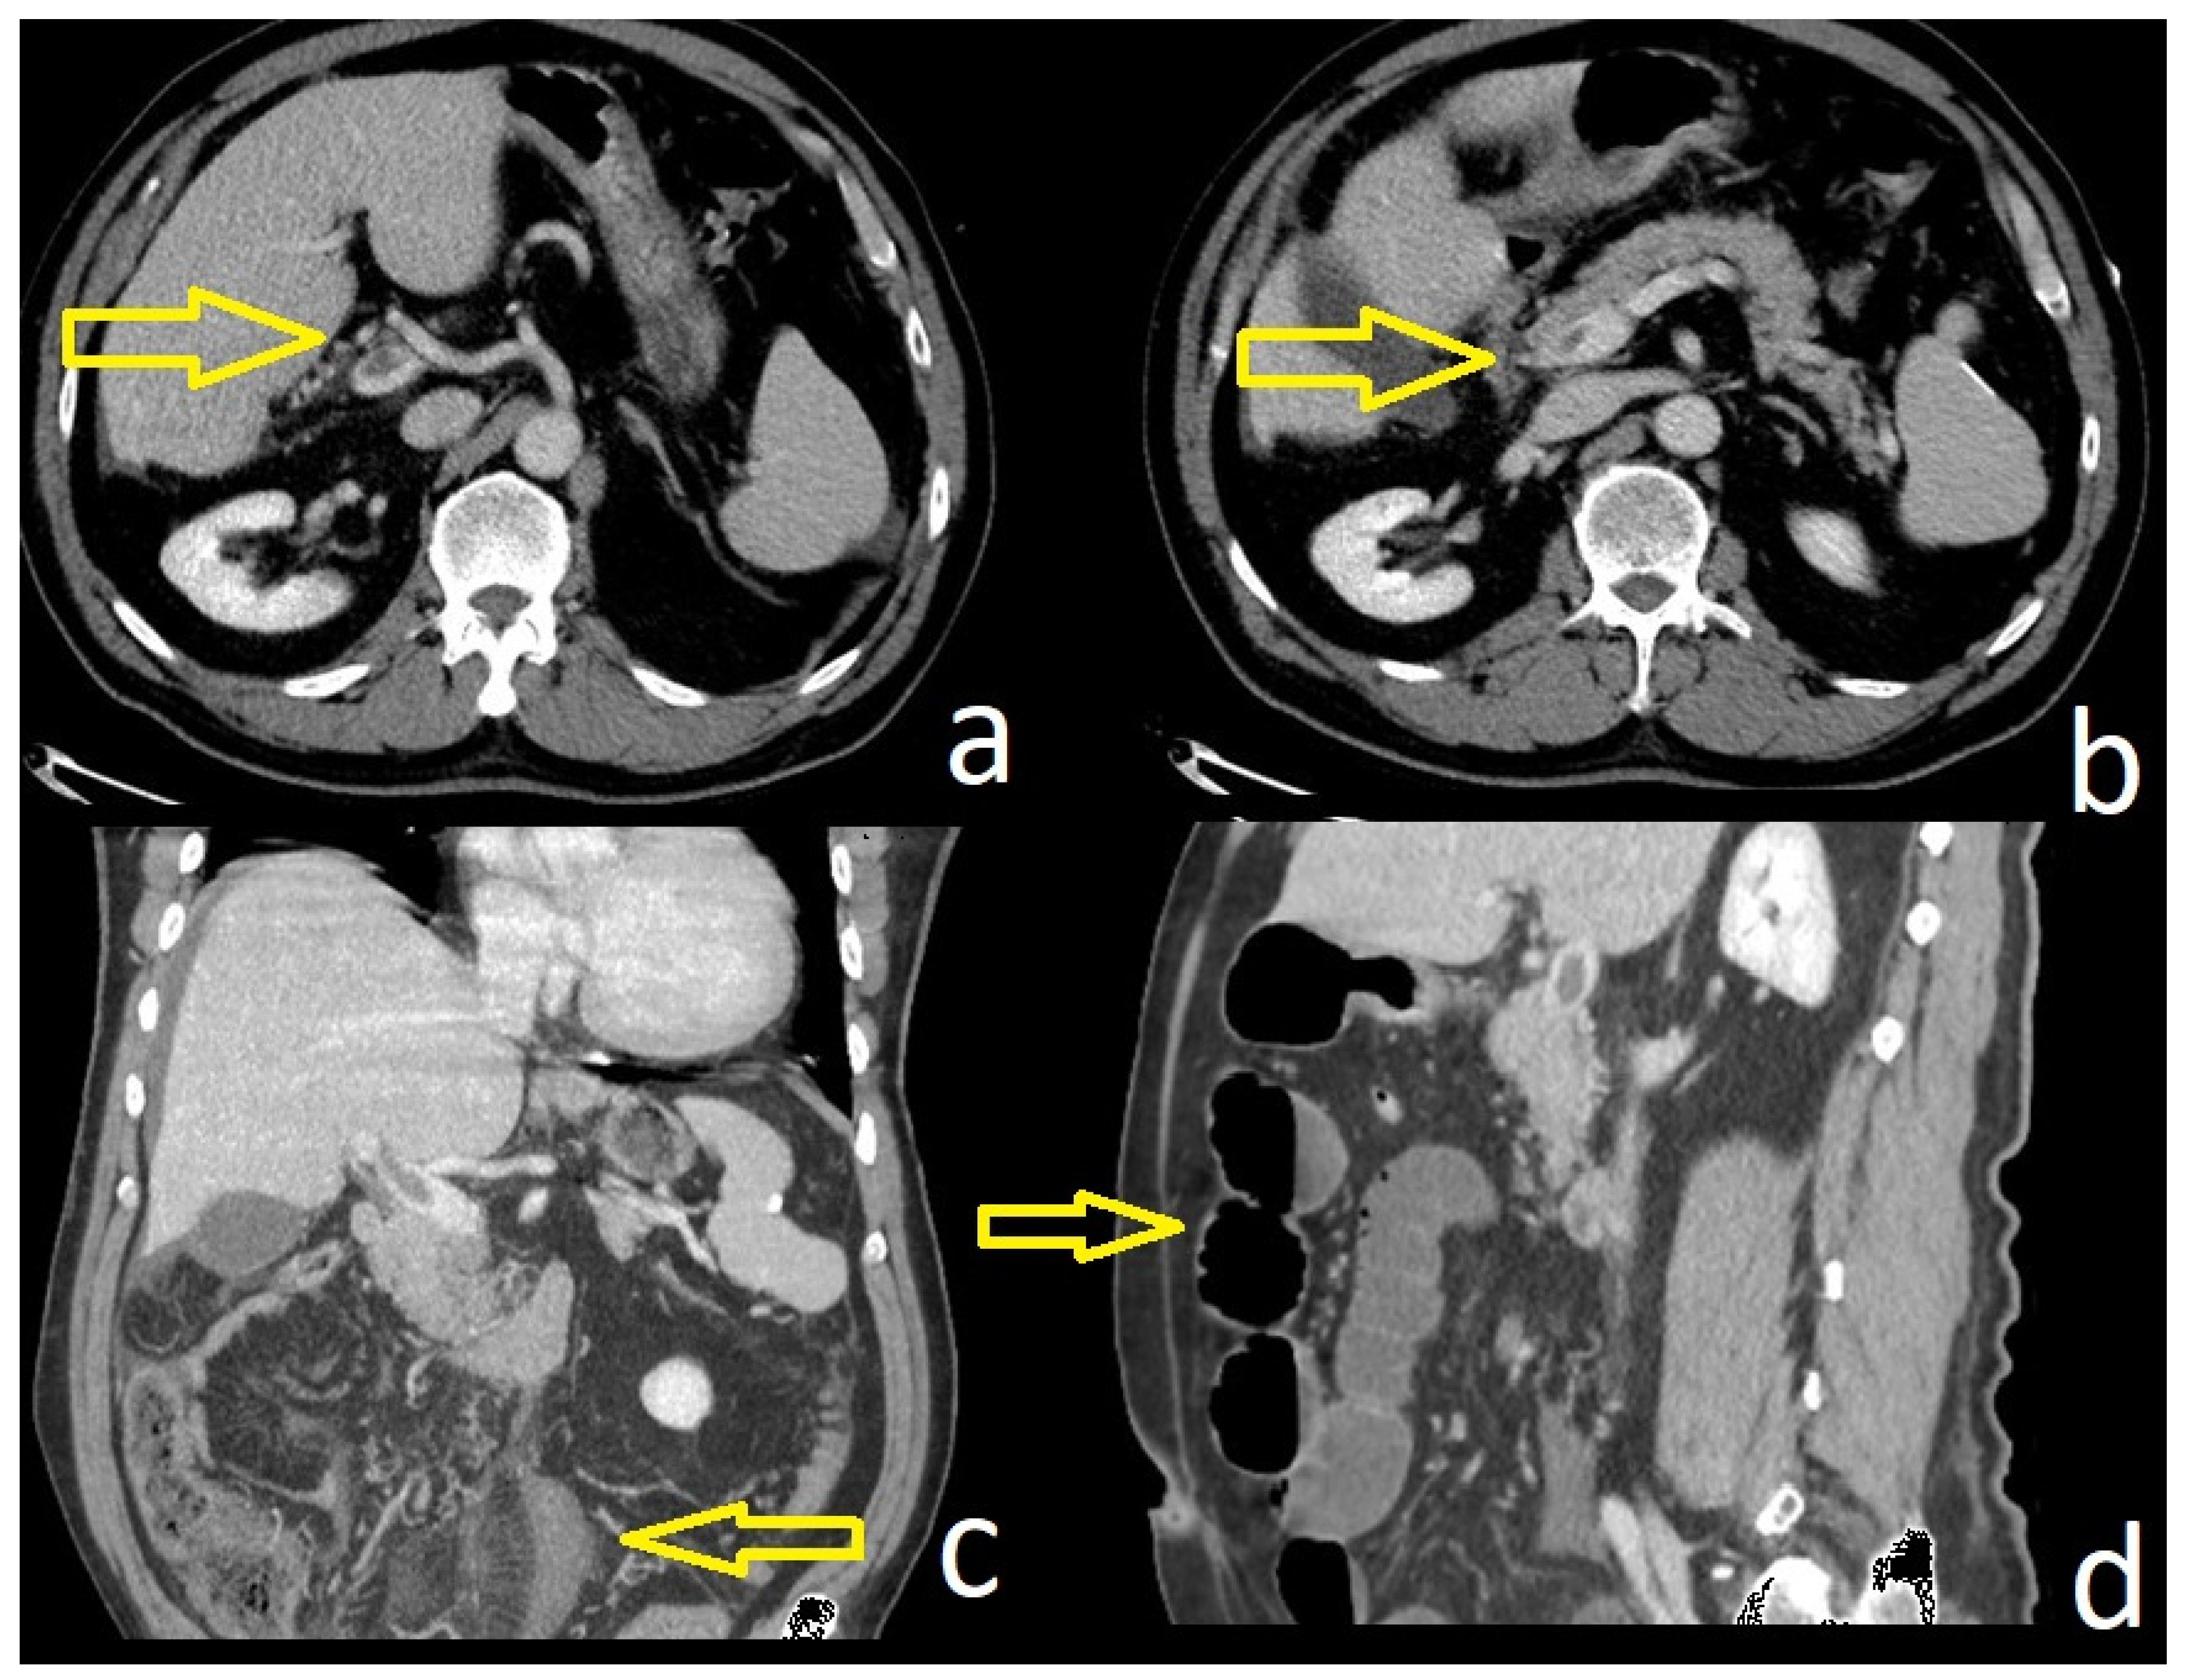

Here we illustrate the importance of CECT, which describes not only the characteristics of the thrombosis but also the consequence since there is ischemia of the distal ileal loops—see Figure 1.

As the clinical presentation of MVT is usually nonspecific, a CECT scan of the abdomen is often required for its diagnosis. CECT presents over 90% sensitivity for the diagnosis of MVT [23]. Along with venous thrombosis, CECT can also assess intestinal ischemia, which provides information for selecting eligible patients for a conservative approach. The detection of the presence of collaterals in a CECT scan of the abdomen helps in differentiating acute MVT from chronic MVT [15]. MR cholangiography coupled with MR portography is a non-invasive technique that allows the detection of biliary cholangiopathy in patients with chronic PVT [24].

Figure 1. CECT aspects of a patient with concomitant PVT and MVT (a,b); ileal loops with edema (c) and ileus (d).